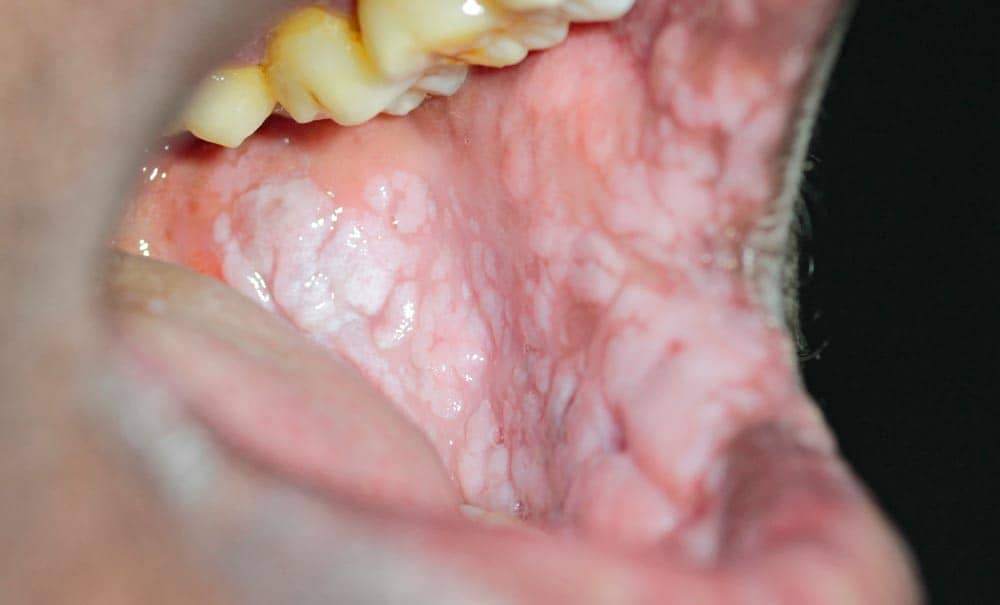

تصویر و شکل ظاهری زگیل تناسلی در دهان

زگیلهای دهانی در تصویر و معاینه بالینی ظاهری متفاوت دارند. برای شناخت بهتر این ضایعات، توصیف دقیق ویژگیهای ظاهری آنها ضروری است:

- رنگ: معمولاً همرنگ پوست، سفید، صورتی یا خاکستری است.

- شکل: ممکن است به شکل برجستگیهای کوچک و منفرد، خوشهای شبیه گل کلم، یا ضایعات مسطح دیده شوند.

- بافت: نرم، مرطوب و گاهی زبر.

- اندازه: از چند میلیمتر تا چند سانتیمتر متفاوت است.

- محل: روی زبان، داخل لبها، لثه، کام، لوزهها و ته حلق.

در بسیاری از موارد این زگیلها بدون علامت هستند و فرد مدتها بدون اینکه بداند ناقل ویروس است. به همین دلیل توجه به تصویر و ظاهر ضایعه اهمیت زیادی دارد، هرچند تشخیص قطعی حتماً باید توسط پزشک انجام شود.

زگیل دهانی بر خلاف آفت، یک ضایعه عفونی است که توسط ویروس پاپیلومای انسانی (HPV) ایجاد میشود و از نظر ظاهری کاملاً متفاوت است؛ به شکل برجستگیهای سفید یا گوشتیرنگ با سطح ناهموار و زگیلمانند روی زبان، لبها، کام یا لوزهها دیده میشود. زگیل دهانی معمولاً بدون درد است و خودبهخود از بین نمیرود، بلکه نیاز به درمان پزشکی (لیزر، کرایوتراپی یا جراحی) دارد. مهمترین تفاوت این است که زگیل دهانی از طریق تماس مستقیم (بوسیدن یا رابطه جنسی دهانی) به دیگران منتقل میشود، در حالی که آفت کاملاً غیرمسری است.